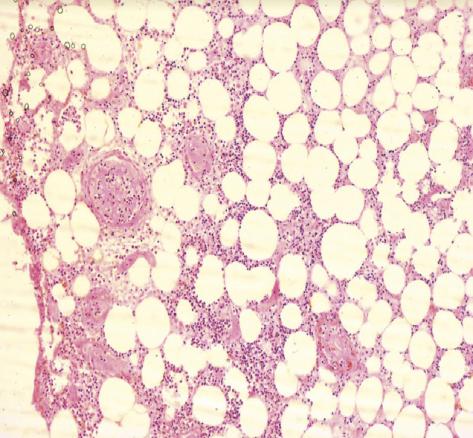

Cette femme de 70 ans, de faible niveau socio-économique, obèse et diabétique de type 2 depuis 20 ans et sous insuline depuis 10 ans, consultait aux urgences pour une douleur de la fosse iliaque gauche. Elle était consciente, tachycarde, fébrile (39,5 °C), et sa glycémie capillaire était à 1,8 g/dL sans cétose. L’examen abdominal notait un placard érythémato-érosif chaud de la fosse iliaque gauche centré par une nécrose bien limitée en carte de géographie (fig. 1 ). La patiente rapportait avoir injecté l’insuline à ce même endroit depuis 3 ans. Le bilan biologique montrait une glycémie à 1,6 g/dL, une hyperleucocytose à 14 500/mm3, une CRP à 130 mg/L et une procalcitonine normale. L’échographie et la tomodensitométrie abdominale montraient un épaississement de la paroi abdominale sans abcès ni collections profondes. Le diagnostic retenu était celui de fasciite nécrosante. Cette patiente était traitée par une antibiothérapie à large spectre avec mise à plat et excision large. L’histologie mettait en évidence des thromboses septiques (fig. 2 ) ainsi qu’une nécrose étendue du derme (fig. 3 ).